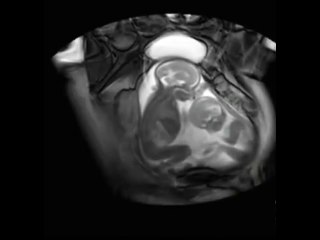

Video Title: Twin babies fight | Amazing Twins | Twins Brothers Fight and mix up

Welcome to the world of caring for twins. It is awesome and exhausting at the same time.